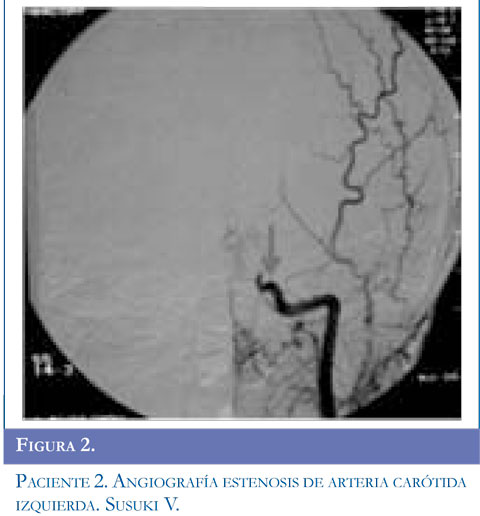

Ingresa al servicio de urgencias por presentar alteración de la marcha dado por disminución de la fuerza en hemicuerpo derecho y dificultad para el habla, acompañado de movimientos clónicos de miembro superior derecho, sin perdida de conciencia la mirada de 10 segundos de duración, se repiten en 5 oportunidades y ceden con benzodiacepinas. Se inició manejo anticonvulsivante. Al examen tenía parálisis facial derecha periférica, hemiparesia derecha con hiperreflexia músculotendinosa, disimetría, disdiadococinesia ipsilateral y afasia motora. Se realizó TAC simple de cráneo y contrastado con lesión gangliobasal izquierda de características isquémicas. Presentó clonias de brazo y aumento de la debilidad faciobraquial derecha, hemianopsia heterónima derecha, se realizó RMC con hipodensidad parieto temporal izquierda compatible con lesión isquémica en territorios de arteria cerebral media izquierda. Se inició enoxaparina1mg/k/dosis y calcio antagonista. El perfil hematológico fue normal. La panangiogra-fía evidenció enfermedad de Moyamoya estadio V de Suzuki. Valorado por neurocirugía se consideró manejo quirúrgico y el día 19 del cuadro clínico se realizó encefaloduroarteriosinangiosis. En la actualidad tiene afasia motora en mejoría, hemiparesia derecha y componente distónico ipsilateral, hiperre-flexia derecha, continúa manejo con fisiatría, terapia física, ocupacional y del lenguaje. Figuras 1,2 y 3.